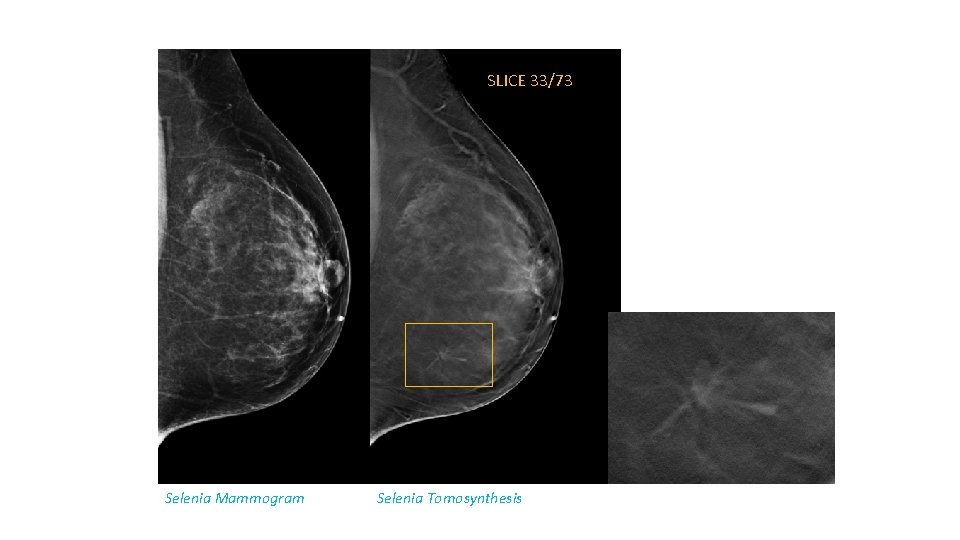

SLICE 33/73 Selenia Mammogram Selenia Tomosynthesis

Tomosynthesis in Increasing PPV • Dense breast • Architectural distortion detection • Circumscribed masses – margins evaluation